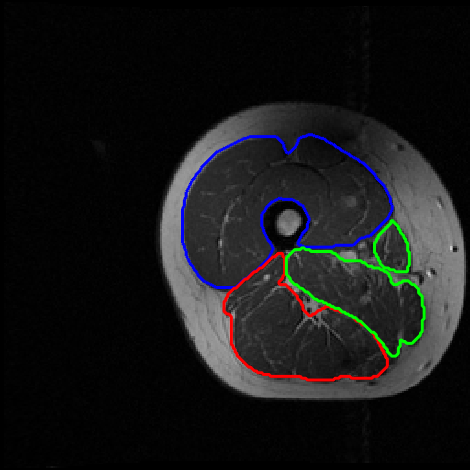

4.3 Results for thigh muscle MR images

Accurate segmentation of various thigh muscles plays a vital role in assessing musculoskeletal disorders like osteoarthritis. However, this task is difficult because of unclear boundaries and the similar intensity and texture among the muscles. The segmentation partitioned the thigh region into four main clusters: the quadriceps, hamstrings, other muscle groups, and remaining tissues. An example muscle MRI is presented in Fig. 5. Thigh muscle MR images contains 75 slices, each sized at 256×256256\times 256. In our experiments, 45 labeled exams are used for training, with the remaining 30 reserved for validation. The training dataset includes nn fully annotated images, with pixel-wise labels unavailable for the remaining 45n45-n. Table 2 provides the results. Fig. 6 illustrates the segmentation outputs produced by various models. As shown in Fig. 6, other methods struggle to accurately distinguish between different muscle categories. In contrast, the segmentation produced by our method aligns more closely with the ground truth and differentiates each muscle category more precisely, avoiding inter-class segmentation errors.

Refer to caption

Figure 5: Example T1-weighted thigh MR image. Left: original image. Right: expert-annotated segmentation with distinct colors indicating quadriceps (blue), hamstrings (red), and other muscles (green).

(g)

Figure 6: Thigh muscle segmentation results obtained by different approaches. Predicted boundaries are indicated in red, blue, and green, and ground truth contours are highlighted in yellow.